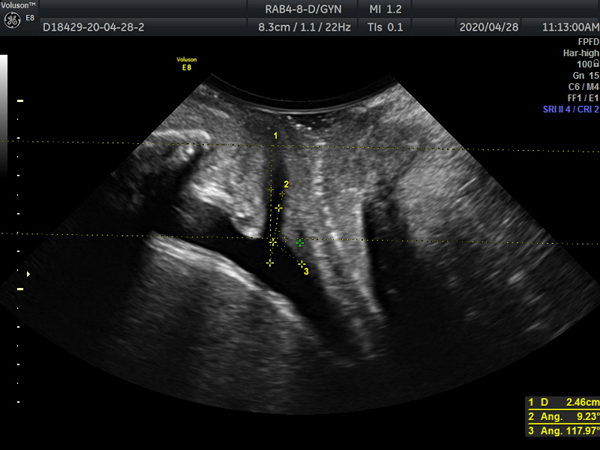

询问完病史,根据患者主述,值班大夫赵云初略判断患者可能是盆底功能障碍性疾病,建议患者行“盆底超声检查”,最终通过三维/四维超声确诊了患者的病症--GreenIII型膀胱膨出,盆底肌松弛引起的盆底功能障碍性疾病之一。这个病会引起尿潴留,导致反复泌尿系感染,病因找到了,患者被建议去我院妇科寻求帮助,下一步治疗方向有了,患者对我院工作人员连声道谢。

病因主要是妊娠、绝经后雌激素水平下降等引起盆底支撑结构损伤、松弛及功能障碍,目前在我国发病率较高。准确诊断的基础就在于对盆底结构及功能的准确认识,很多时候单纯的临床普通检查并不能获得盆底解剖以及功能改变的详细信息。 而盆底超声通过盆底组织的二维及三维/四维超声检查,获得盆底完整的声像图,可以比较直观的显示盆底各脏器的空间关系并明确诊断。

盆底超声不但可以直接观察盆底变化情况,而且膀胱移动度、尿道倾斜角、膀胱后角、尿道内口漏斗是否形成、子宫有无脱垂、直肠有无膨出、有无肠疝、肛门括约肌及肛提肌有无损伤等还可作为盆底情况客观影像学指标。